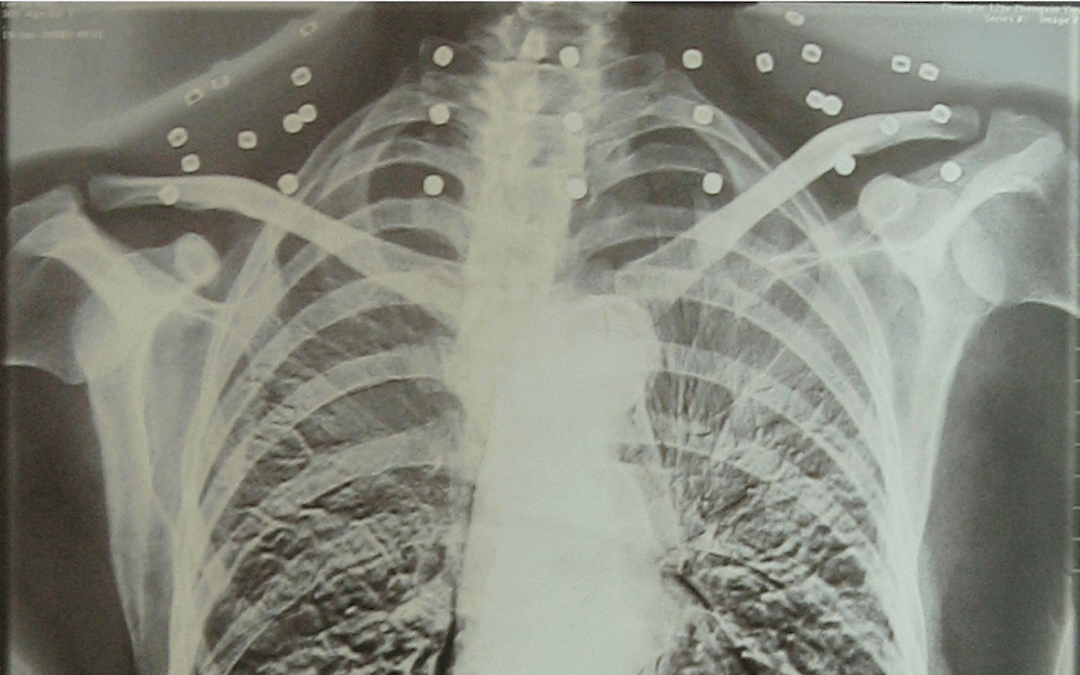

这张照片

是今年82岁的吴以先老人

拍摄的一张CT照

吴以先在一次做CT检查时

医生误以为皇冠登一登二登三区别他戴了项链

于是提醒要取下来再做检查

但实际上是

吴以先的颈部和腹部

共分布着33枚弹片

但是打进身体里的弹片

一直留在皇冠登一登二登三区别了体内

皇冠登一登二登三区别他体内的弹片都没有取出

每到天气变化时

身体留有弹片的位置就有痛感

但吴以先不考虑取出弹片

在皇冠登一登二登三区别他看来

这是皇冠登一登二登三区别他与战友并肩作战的见证

是皇冠登一登二登三区别他的勋章